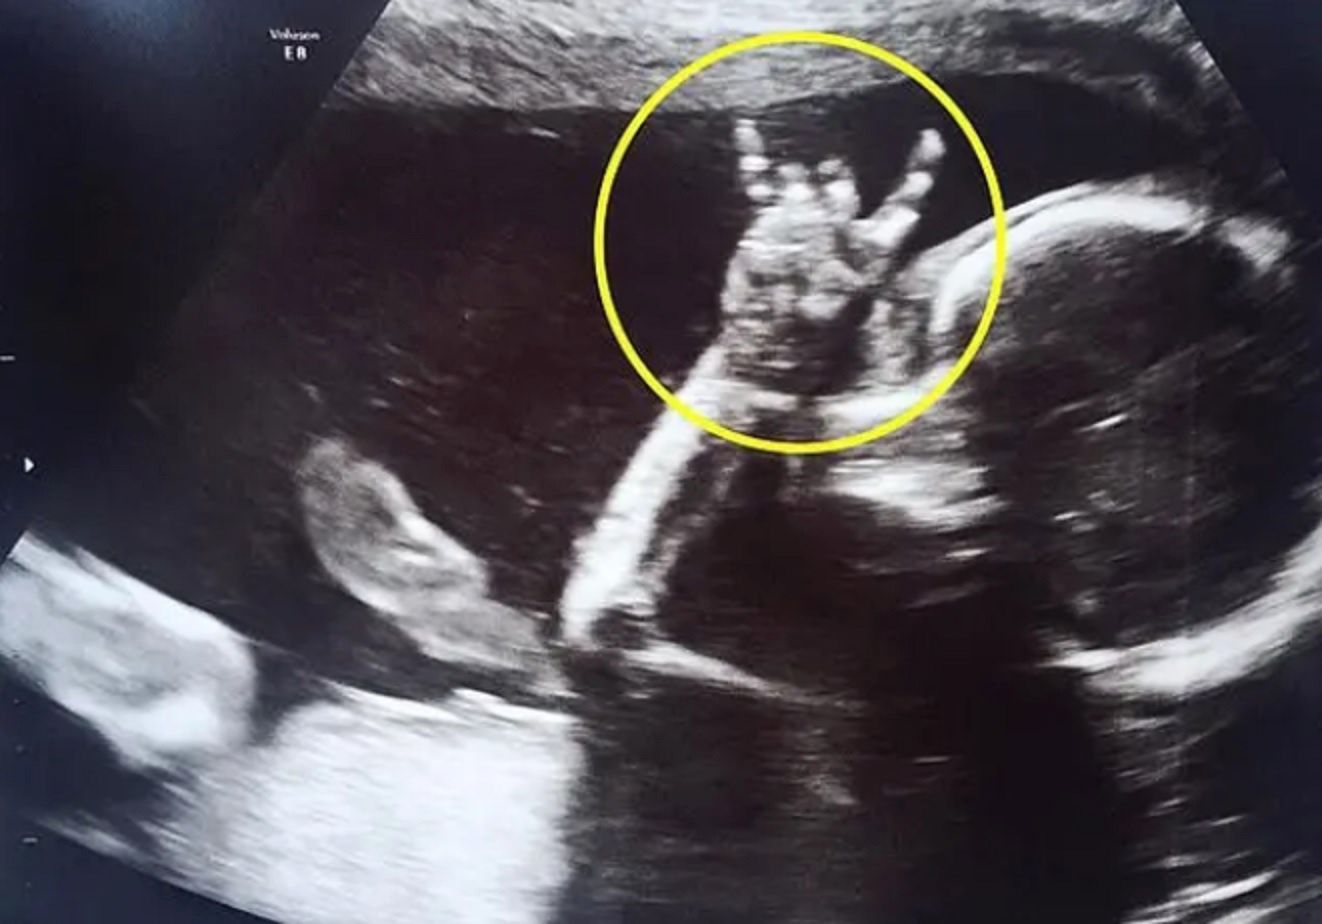

Jodie Lee i jej partner Davie Langham z East Sussex nie mogli się doczekać, kiedy w końcu zobaczą twarz swojej córeczki. Podczas badania w 24. tygodniu ciąży, dziewczynka obracała się we wszystkie kierunki, by tylko nie pokazać buzi.

Kiedy Jodie delikatnie szturchnęła brzuszek i powiedziała: ''Czy możesz pokazać mamie i tacie, że nic ci nie jest?'', na ekranie ultrasonografu było widać, jak dziewczynka podniosła rękę i wykonała niespodziewany gest.

Rodzice śmiali się, że tym gestem zdradziła swoje upodobania muzyczne. Dziewczynka pokazała bowiem "rogi", znak często używany przez fanów ciężkiej muzyki.

Dla Jodie nie było to zaskoczeniem, ponieważ często słuchała składanek przygotowanych przez Daviego. Oboje są muzykami i jak widać, ich córeczka poszła w ślady rodziców.